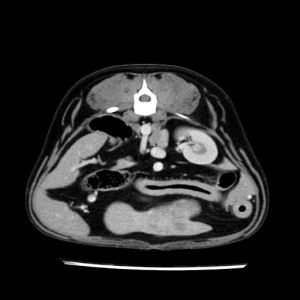

La lesione focale epatica , la ceus,la Tac e il chirurgo .